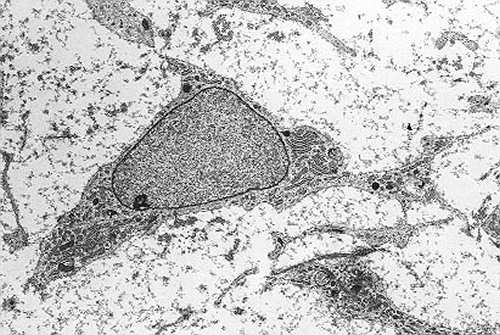

Células madre mesenquimales. (Foto: Robert M. Hunt)

“Las células madre mesenquimales no son rechazadas, tienen excelentes propiedades inmunomoduladoras y el proceso de preparación se reduce de cinco semanas a cinco días, con el consiguiente ahorro que esto supone”, apunta la doctora Ana Sánchez. Su empresa, Citospin, tiene solicitada la patente internacional sobre el protocolo de distribución de células madre mesenquimales de Valladolid (MSV), como han llamado al producto.